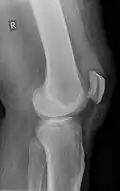

Teilriss der Sehne, die auch im Röntgenbild aufgetrieben (eingeblutet) sichtbar ist -